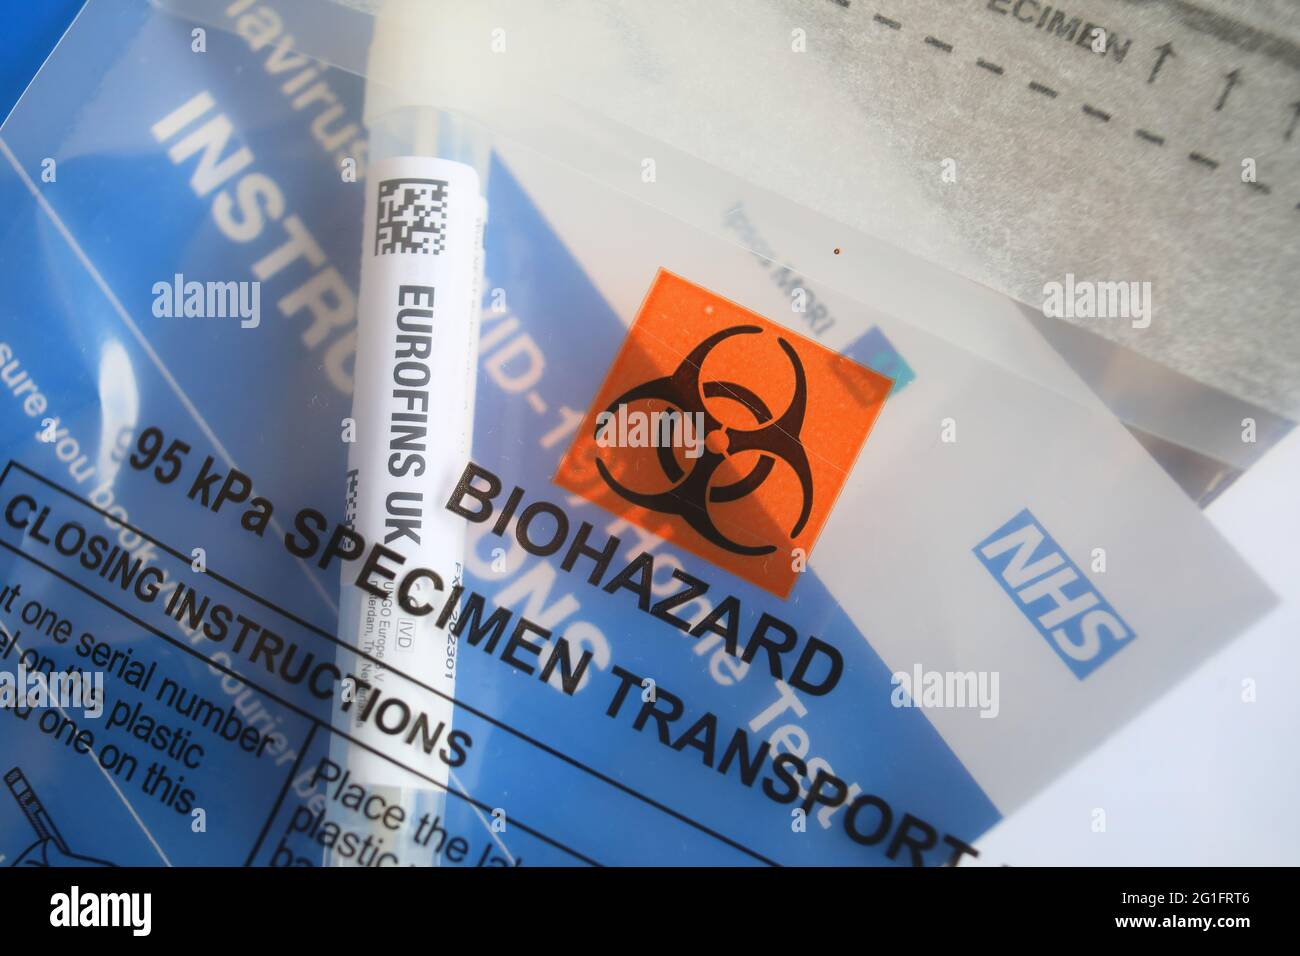

PCR at home test, UK Stock Photohttps://www.alamy.com/image-license-details/?v=1https://www.alamy.com/pcr-at-home-test-uk-image431221852.html

PCR at home test, UK Stock Photohttps://www.alamy.com/image-license-details/?v=1https://www.alamy.com/pcr-at-home-test-uk-image431221852.htmlRM2G1FRTC–PCR at home test, UK

PCR at home test, UK Stock Photohttps://www.alamy.com/image-license-details/?v=1https://www.alamy.com/pcr-at-home-test-uk-image431221846.html

PCR at home test, UK Stock Photohttps://www.alamy.com/image-license-details/?v=1https://www.alamy.com/pcr-at-home-test-uk-image431221846.htmlRM2G1FRT6–PCR at home test, UK

PCR at home test, UK Stock Photohttps://www.alamy.com/image-license-details/?v=1https://www.alamy.com/pcr-at-home-test-uk-image431221848.html

PCR at home test, UK Stock Photohttps://www.alamy.com/image-license-details/?v=1https://www.alamy.com/pcr-at-home-test-uk-image431221848.htmlRM2G1FRT8–PCR at home test, UK